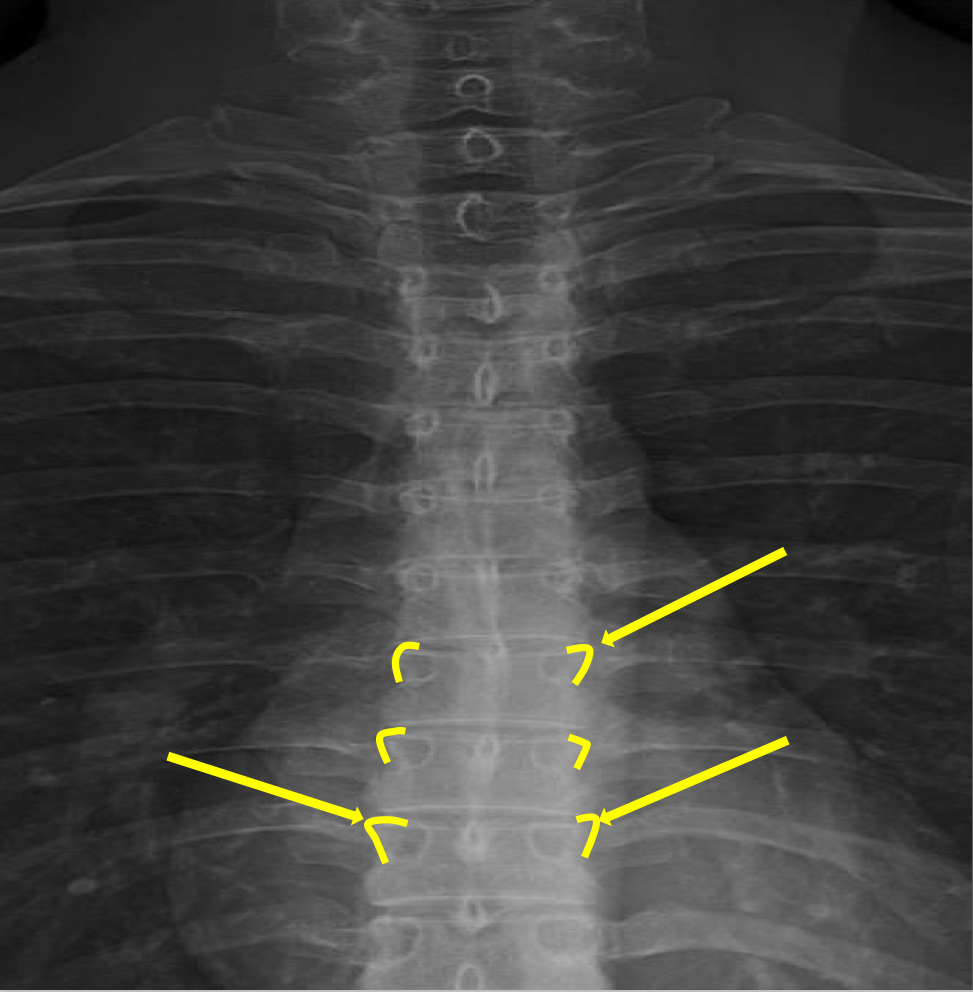

What view is this?

AP (Anterior to Posterior) Thoracic

What is this?

Junction of Laminae

What is this?

Pedicle Shadows

What is this?

Vertebral Waist

What is this?

Inferior Endplate Tips

What is this?

Superior Endplate Tips

What is this?

Disc Spaces